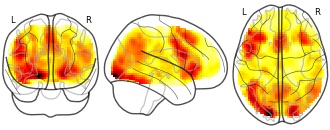

"name": "Multi_VBMsmaller_fMRIdecreased",

"description": "Multi-modal analysis in BPD. Brain regions exhibiting smaller gray matter and decreased activation during emotion processing in BPD compared to healthy controls. Note: Results were thresholded at p<.0025. Note2: Results were updated (see Erratum for this publication).",